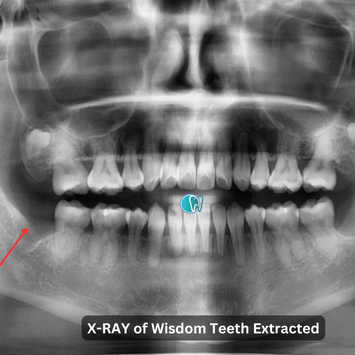

Surgical Removal of Wisdom Teeth #38, #48

Patient presents with pain and swelling, with teeth #38 and #48 completely buried under the gingiva and impacted. Patient requested removal of both teeth.

Impacted teeth #38 and #48, buried completely under the gingiva.

Post-operative CBCT taken.

No tooth remnants noted.

Inferior dental nerve (IDN) and maxillary sinus intact, not involved in surgery.